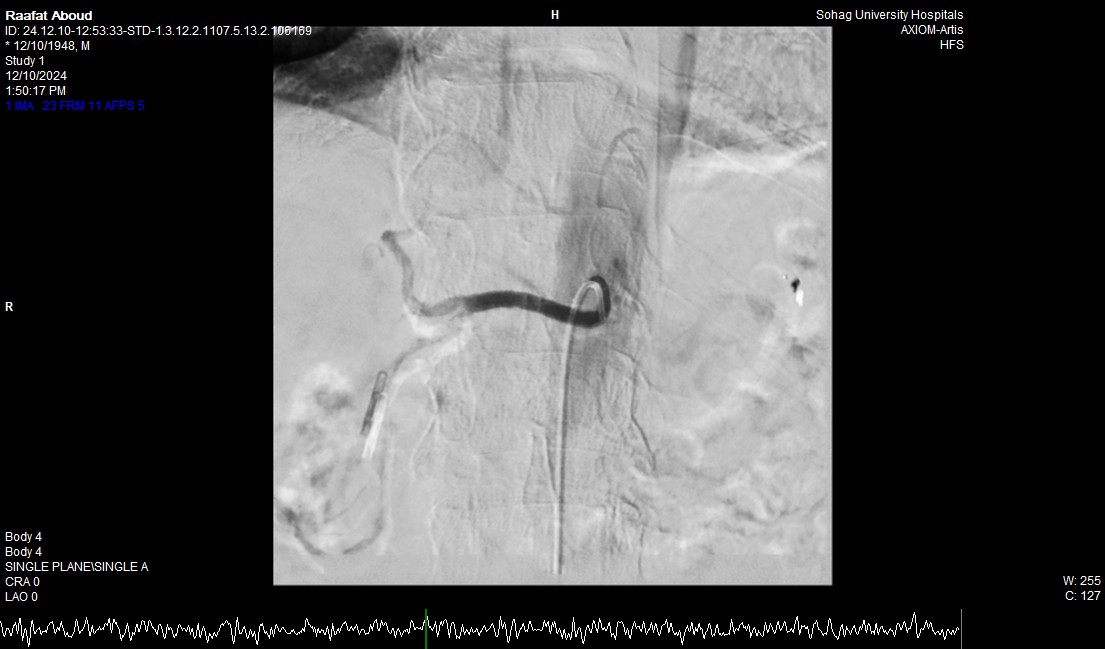

صرح الدكتور حسان النعماني رئيس جامعة سوهاج ان فريق طبي بوحدة الجهاز الهضمي والكبد بقسم الباطنة العامة ووحدة الاشعة التداخلية بقسم الاشعة نجح في انقاذ حياه مريض يبلغ من العمر ٧٥ عاماً له تاريخ مرضي ويعاني بقصور بوظائف الكلي وتليف بالكبد، حيث نجح الفريق في ايقاف نزف شرياني حاد من خلال إجراء التدخل السريع بإستخدام المنظار والقسطره الشريانيه العلاجيه بالاشعة التداخلية، مثمناً دور المستشفيات الجامعية في خدمة المرضي وما تمتلكه من الكوادر الطبية ذوي الخبرات التي تؤهلها للتعامل مع مثل هذه الحالات الطارئة باحترافية ومهارة فائقة.

وأضاف الدكتور أحمد كمال المدير التنفيذي للمستشفيات الجامعية انه بعد اجراء الفحوصات للمريض تبين وجود قرحة كبيرة بالاثني عشر وشريان نازف، حيث نجح الفريق في التحكم المبدئي بالنزيف عن طريق تركيب مشبك معدني بالمنظار وحقن للقرحة النازفة، ثم تم استدعاء فريق أطباء وحدة الاشعة التداخلية علي الفور وتم عمل غلق للشريان النازف بشكل عاجل من خلال جهاز القسطرة.

وأوضح الدكتور محمد زاكي رئيس قسم الأشعة أن مثل هذه الحالات تعد من الطوارئ الطبية الخطيرة والتي تستوجب عمل قسطره شريانية عاجلة لغلق الشرايين النازفه مشيراً أن وحدة الأشعة التداخلية تم تزويدها بجهاز أشعه محوري متقدم لاجراء مثل هذه الحالات، وأن هذا النجاح هو نتيجة لتعاون أقسام المستشفي مع وحدة الأشعة التداخليه لتقديم خدمة مميزه للمرضي.